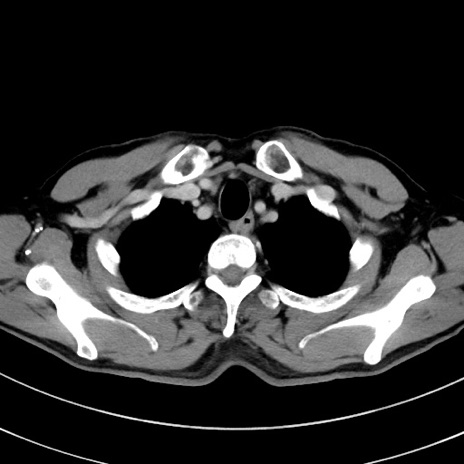

症例8(横断像)

【症例】 60歳代男性

【主訴】 黒色吐物

【現病歴】 4日前から嘔気自覚、2日前の朝食後にも嘔気あり、自分で手で嘔吐反射起こし嘔吐したところ血が混ざっていたため受診。

【既往歴】 5年前汎発性腹膜炎を伴う急性虫垂炎で手術、高血圧、前立腺肥大症、高脂血症

【身体所見】 腹部正中に手術癩痕あり 腹部平坦・軟圧痛なし膨満感あり

【データ】WBC 8400、CRP 4.54